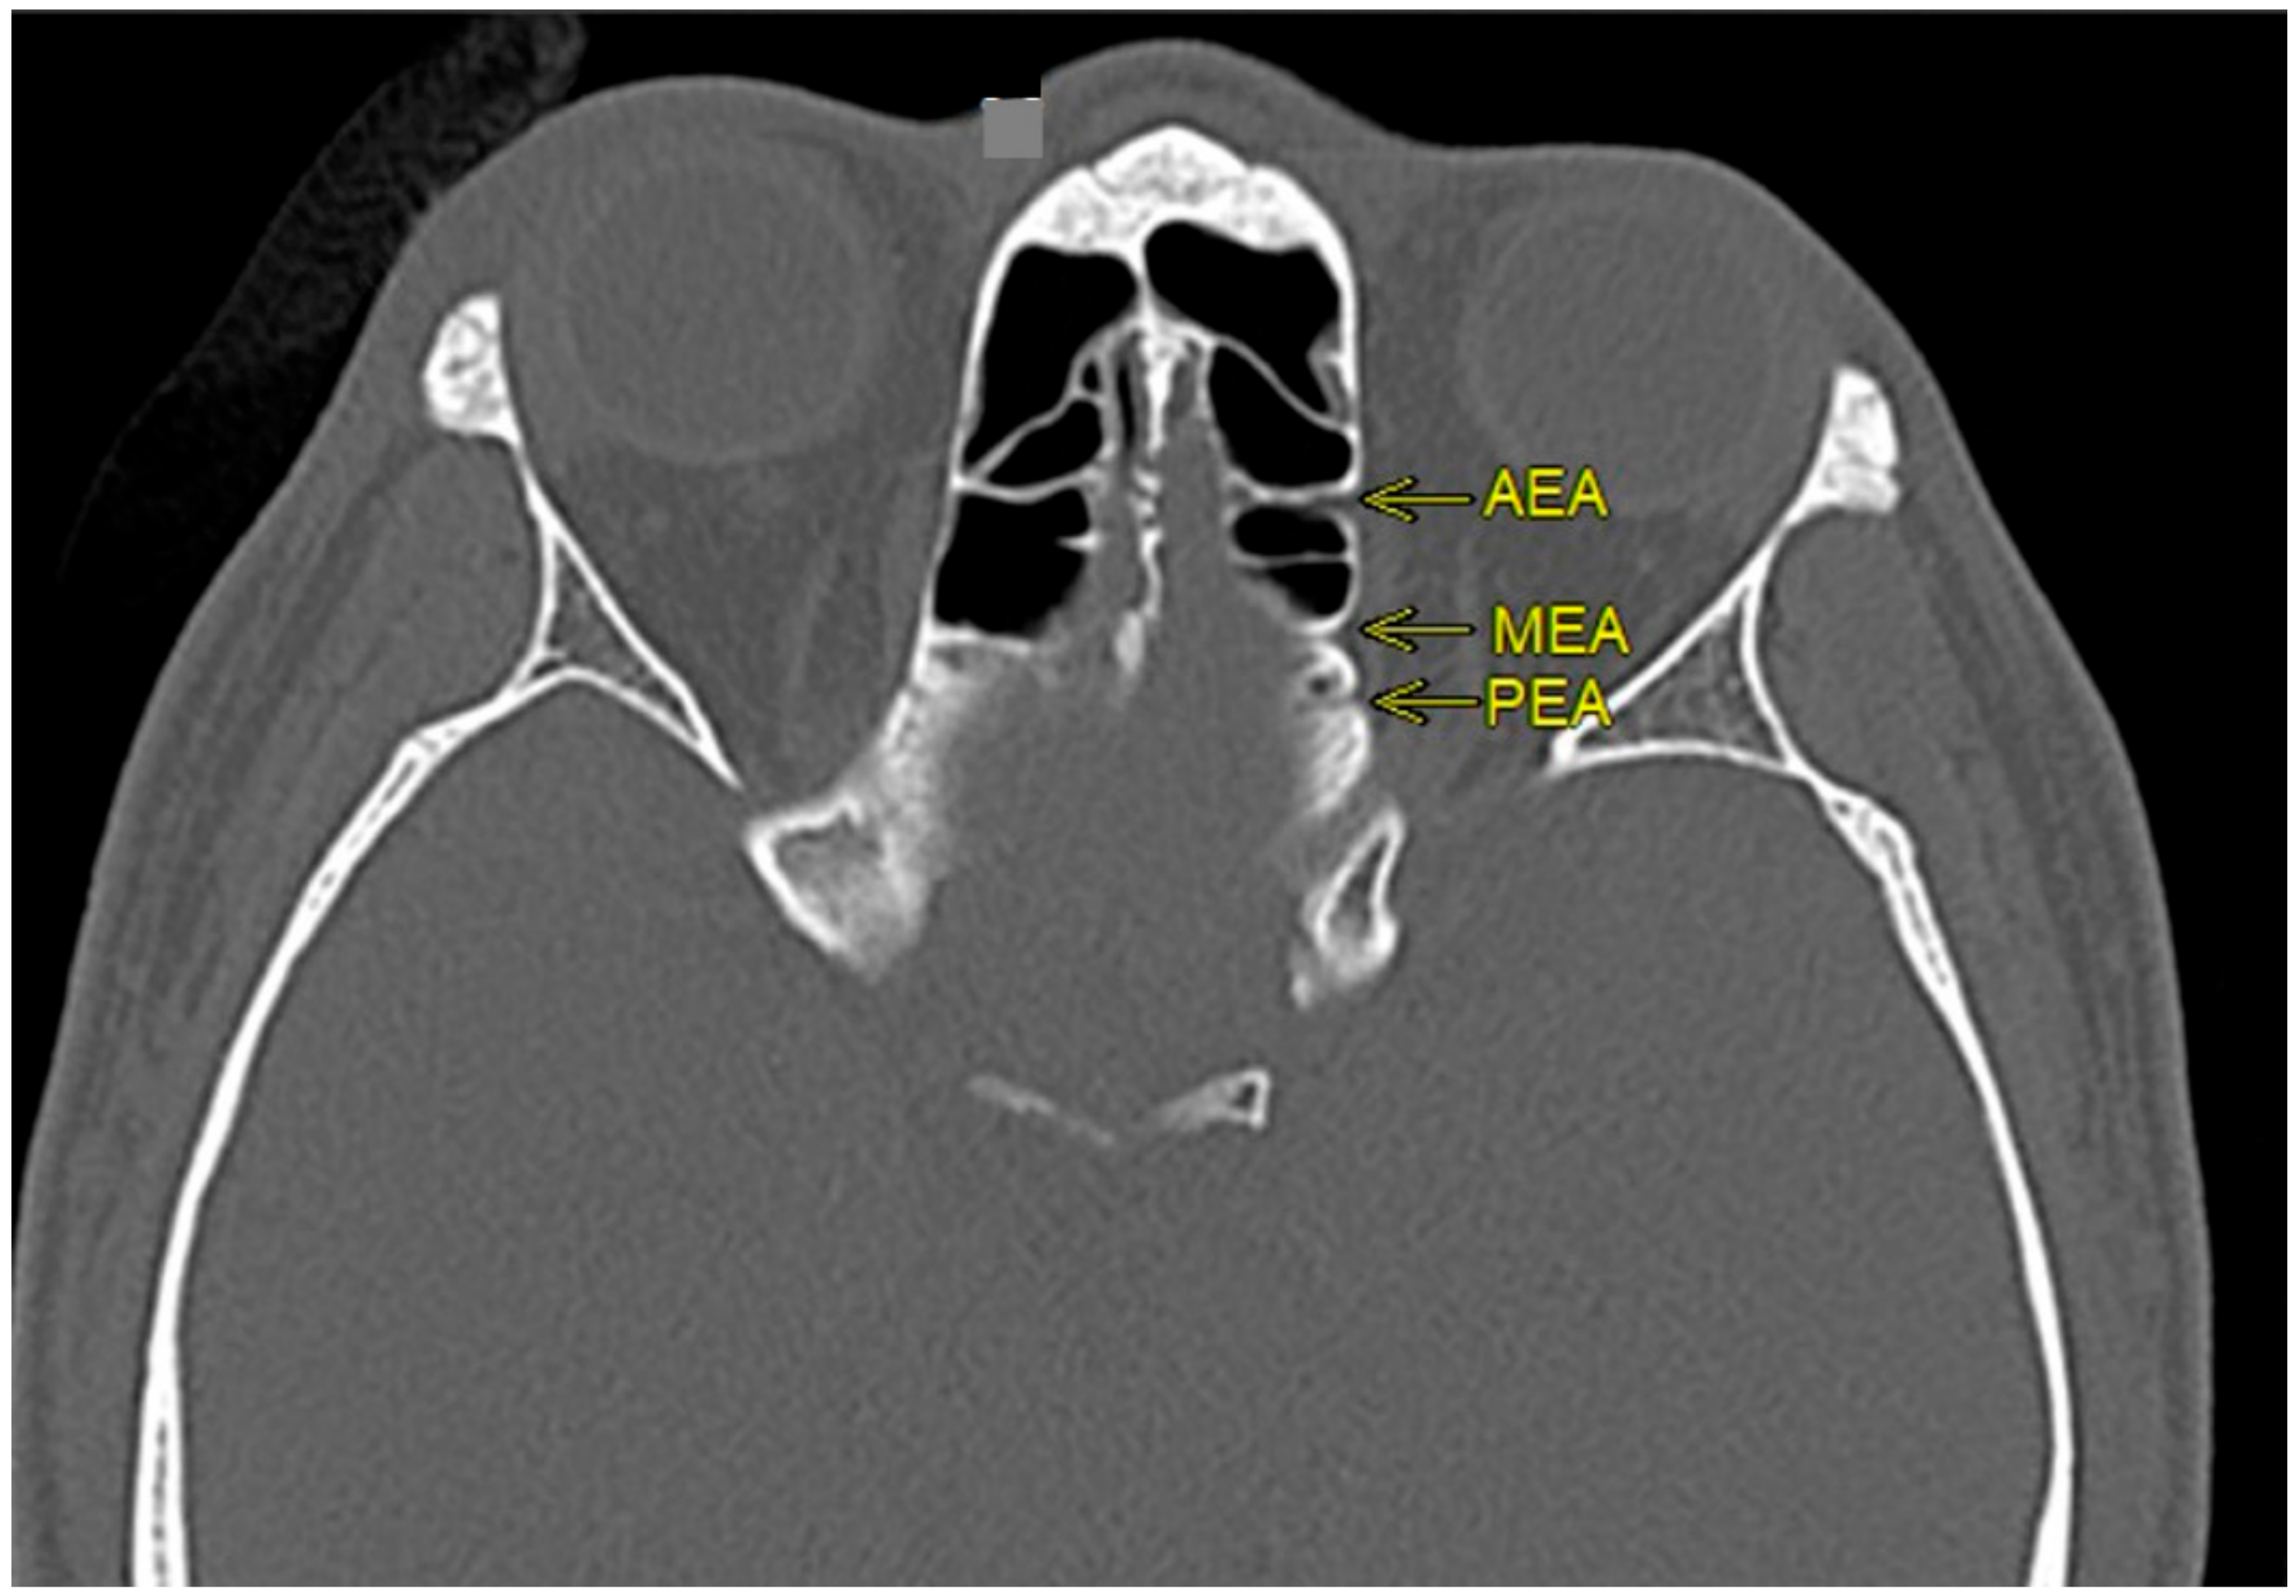

2.2. Evaluation of Anterior Ethmoidal and Middle Ethmoidal Arteries

2.3. Measurement of Anterior Ethmoidal and Middle Ethmoidal Arteries to Related Anatomical Structures